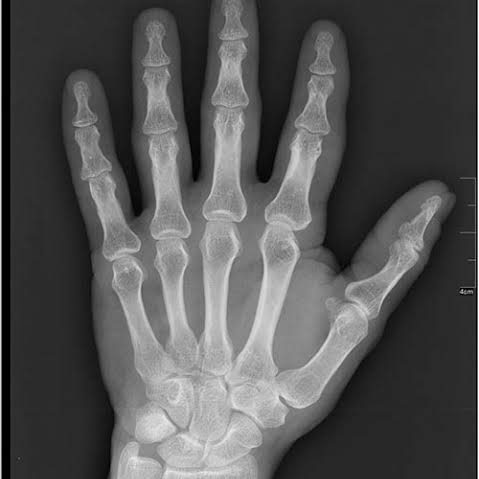

The knowledge of the skeletal maturation and the stage of the growth of the patients seeking orthodontic treatment are of great value in planning efficient orthodontic therapy. However, different craniofacial structures of patient show variation in growth potential. The routine use of hand-wrist radiograph for growth prediction exposes the patient to extra radiation. Cervical vertebrae in the lateral cephalograph have been recommended as an alternative method. The pubertal growth spurt is a vital period in the orthodontic treatment and should be kept in mind when planning orthodontic treatment in growing children. One of the main objectives of taking hand and wrist radiograph is to determine the amount of growth and get used of it in patients with skeletal discrepancy during adolescence. Further, this will help in the selection of the appliances required, the course of the treatment and the retention after active orthodontic therapy.